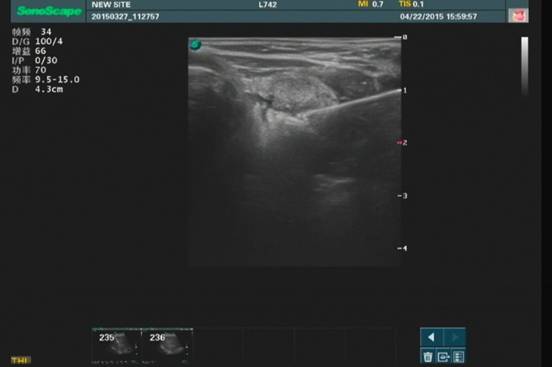

病例1消融术前肿大的甲状旁腺彩超影像

病例1消融中彩超影像

病例1消融术后影像

2例患者术前经超声科精确定位肿大的甲状旁腺,然后在超声引导下将微波刀穿刺入肿大的甲状旁腺中,启动微波仪,图像示甲状旁腺气化增强,组织在微波作用下变性坏死,完成治疗。病例1术后第二天复查甲状旁腺激素示:53.30pg/ml,降钙素:9.6ng/L,指标均已恢复正常,患者术后恢复良好,术后三天出院;病例2仅在术后10分钟后,患者自诉手足麻木及抽搐症状明显缓解。术后第3天,复查甲状旁腺激素253.0 pg/ml,较前明显降低,患者手足麻木及抽搐症状完全消失,顺利出院。